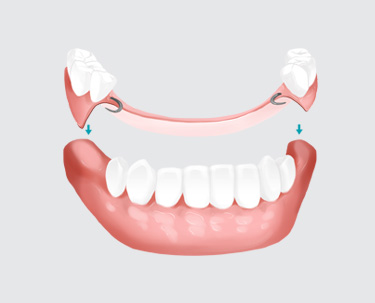

부분 틀니가 필요한 분